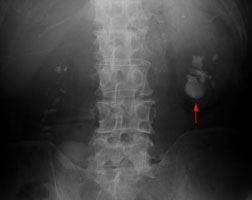

7.巨大腎臓結石(将来手術) |